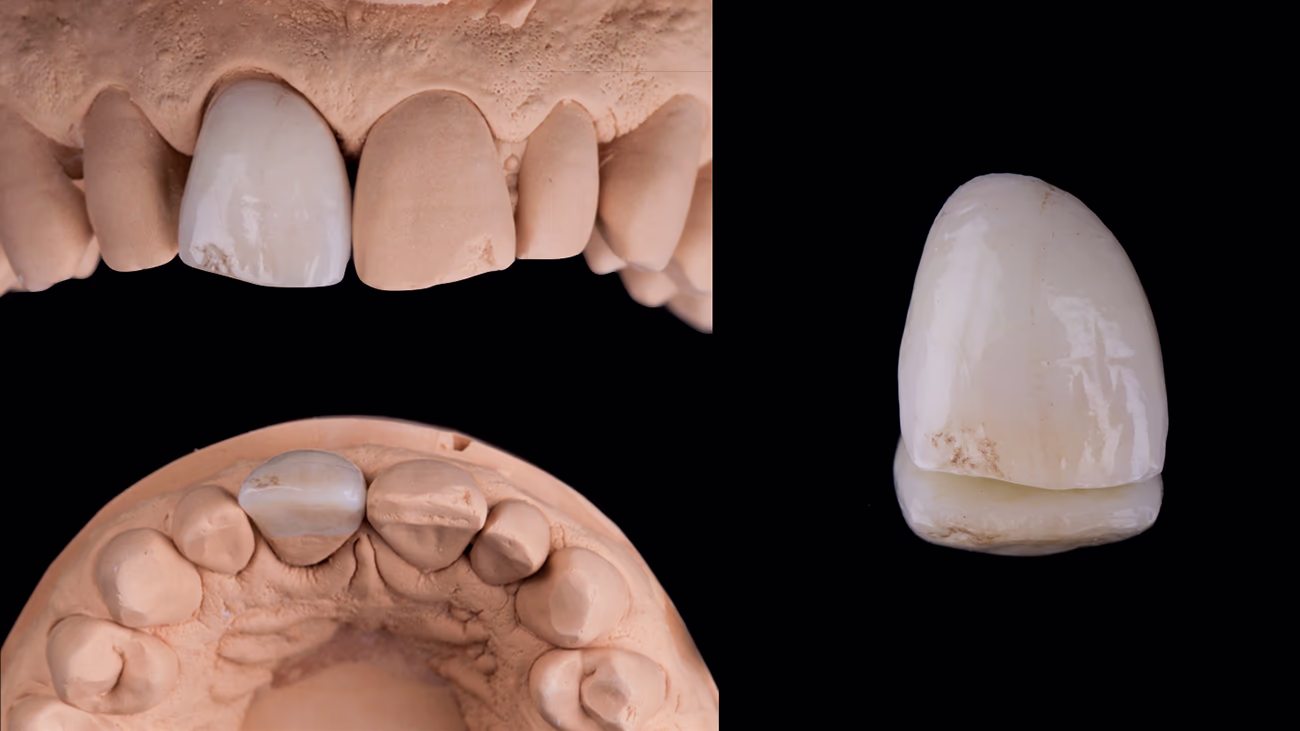

У цьому випадку для відновлення зуба 11 був обраний матеріал літій-дисилікат з пошаровим нанесенням кераміки на вестибулярну по верхню.

Перевагою протоколу eLab є віртуальна примірка та порівняння готової керамічної реставрації зуба 11 і сусіднього зуба 21.

Цифрова примірка за протоко лом eLAB дозволяє зубному техніку проводити оцінку майбутньої ΔE, що відображає різницю між кольором натурального зуба 21 та виготовленої керамічної реcтаврації зуба 11.

Віртуальна примірка в зуботехнічній лабораторії показала значення ΔE 1,21. Відмінність практично непомітна неозброєним оком. У клінічній практиці вважається ідеальним результатом.